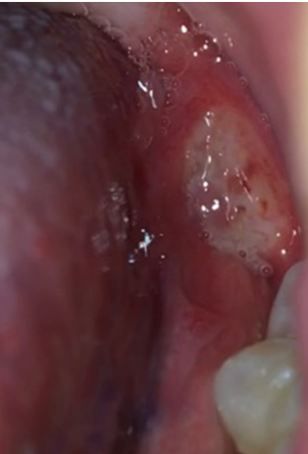

Skin ulcerations have a broad differential. Take this quick quiz to test your knowledge of some difficult diagnoses.